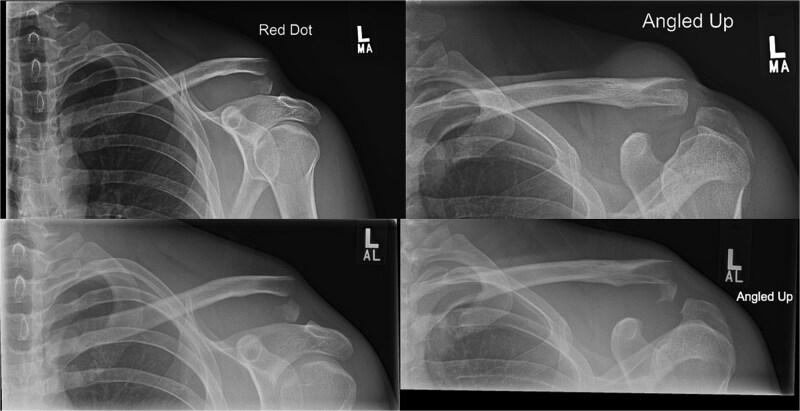

Lateral end clavicle fractures, especially those that are displaced, have a high rate of delayed and non-union. This case series presents three patients with unstable lateral end clavicle fractures successfully treated with TightRope fixation as the sole method of stabilization, demonstrating excellent functional outcomes and minimal complications. The comprehensive literature review reveals mounting evidence with eight reported studies supporting TightRope as an effective standalone treatment option, with the largest published series showing 79% union rates and only 10% complication rates. These findings, combined with the theoretical advantages of avoiding routine hardware removal, lower costs, and compatibility with day-surgery protocols, suggest that TightRope fixation merits serious consideration as a primary treatment modality for appropriately selected patients with lateral end clavicle fractures.

Abstract Image